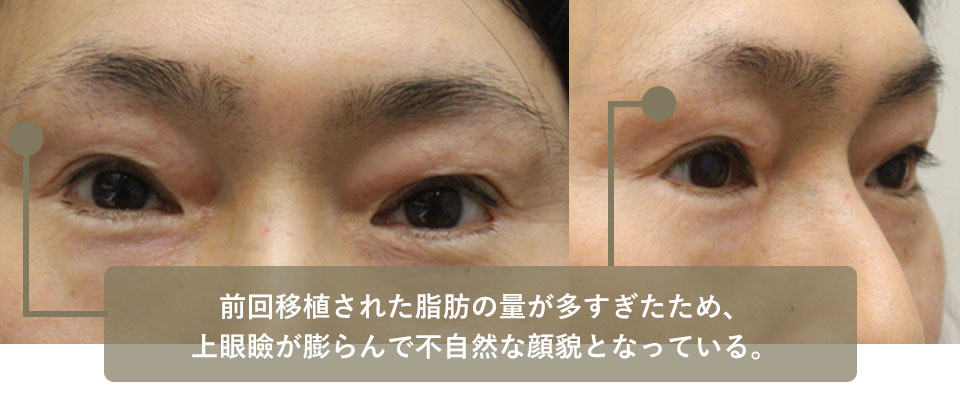

E大学病院形成外科で眼瞼下垂の手術を行ったところ、上眼瞼の凹みが気になった。

東京のF美容外科で鼡径部の脂肪を上眼瞼に移植する手術を2回受けたところ、今度はまぶたが膨らんでしまったため、切除希望で来院。前回移植された脂肪が前方に突出し不自然な目つきになっていました。

少量の皮膚と移植された脂肪の切除を行ったところ、綺麗で自然なまぶたになっています。

| 術前 | 前回移植された脂肪の量が多すぎたため、上眼瞼が膨らんで不自然な顔貌となっている。 |

|---|---|

| 術後 | 皮膚と移植された脂肪の切除、その後二重瞼を作成した。 やや陥凹が目立つが自然な仕上がりになった。 |

| 術前 | 移植された脂肪の量が多すぎたため、上眼瞼(特に内側)が膨らんで不自然な顔貌となっている。 |

|---|---|

| 術後 | 皮膚と移植された脂肪の切除、その後二重瞼を作成した。 やや陥凹が目立つが自然な仕上がりになった。 |